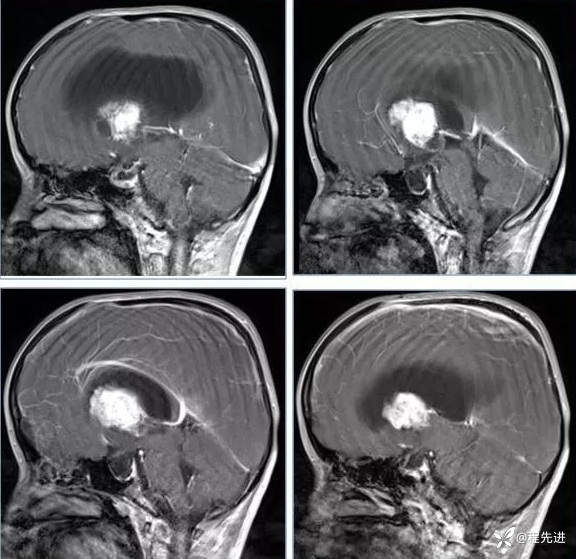

【神经】特别精彩病例|行走不稳2月余

患者性别:男

患者年龄:13岁

主诉:行走不稳2月余

现病史:2个月前患者无明显诱因下出现行走不稳,近期症状逐渐加重,站立不能。病程中患者无意识障碍,无头痛头晕,无明显恶心呕吐、视物旋转、耳鸣、眼球活动障碍等,无尿量增多、泌乳、口干等,体重无明显改变,睡眠可,食欲可,二便正常。

既往史:患者生后8个月和今年出现两次癫痫发作,持续时间不长

个人史:患者自幼失语,智力障碍

专科检查:右侧肢体肌力III-IV级,左侧肢体肌力IV级,肌张力下降